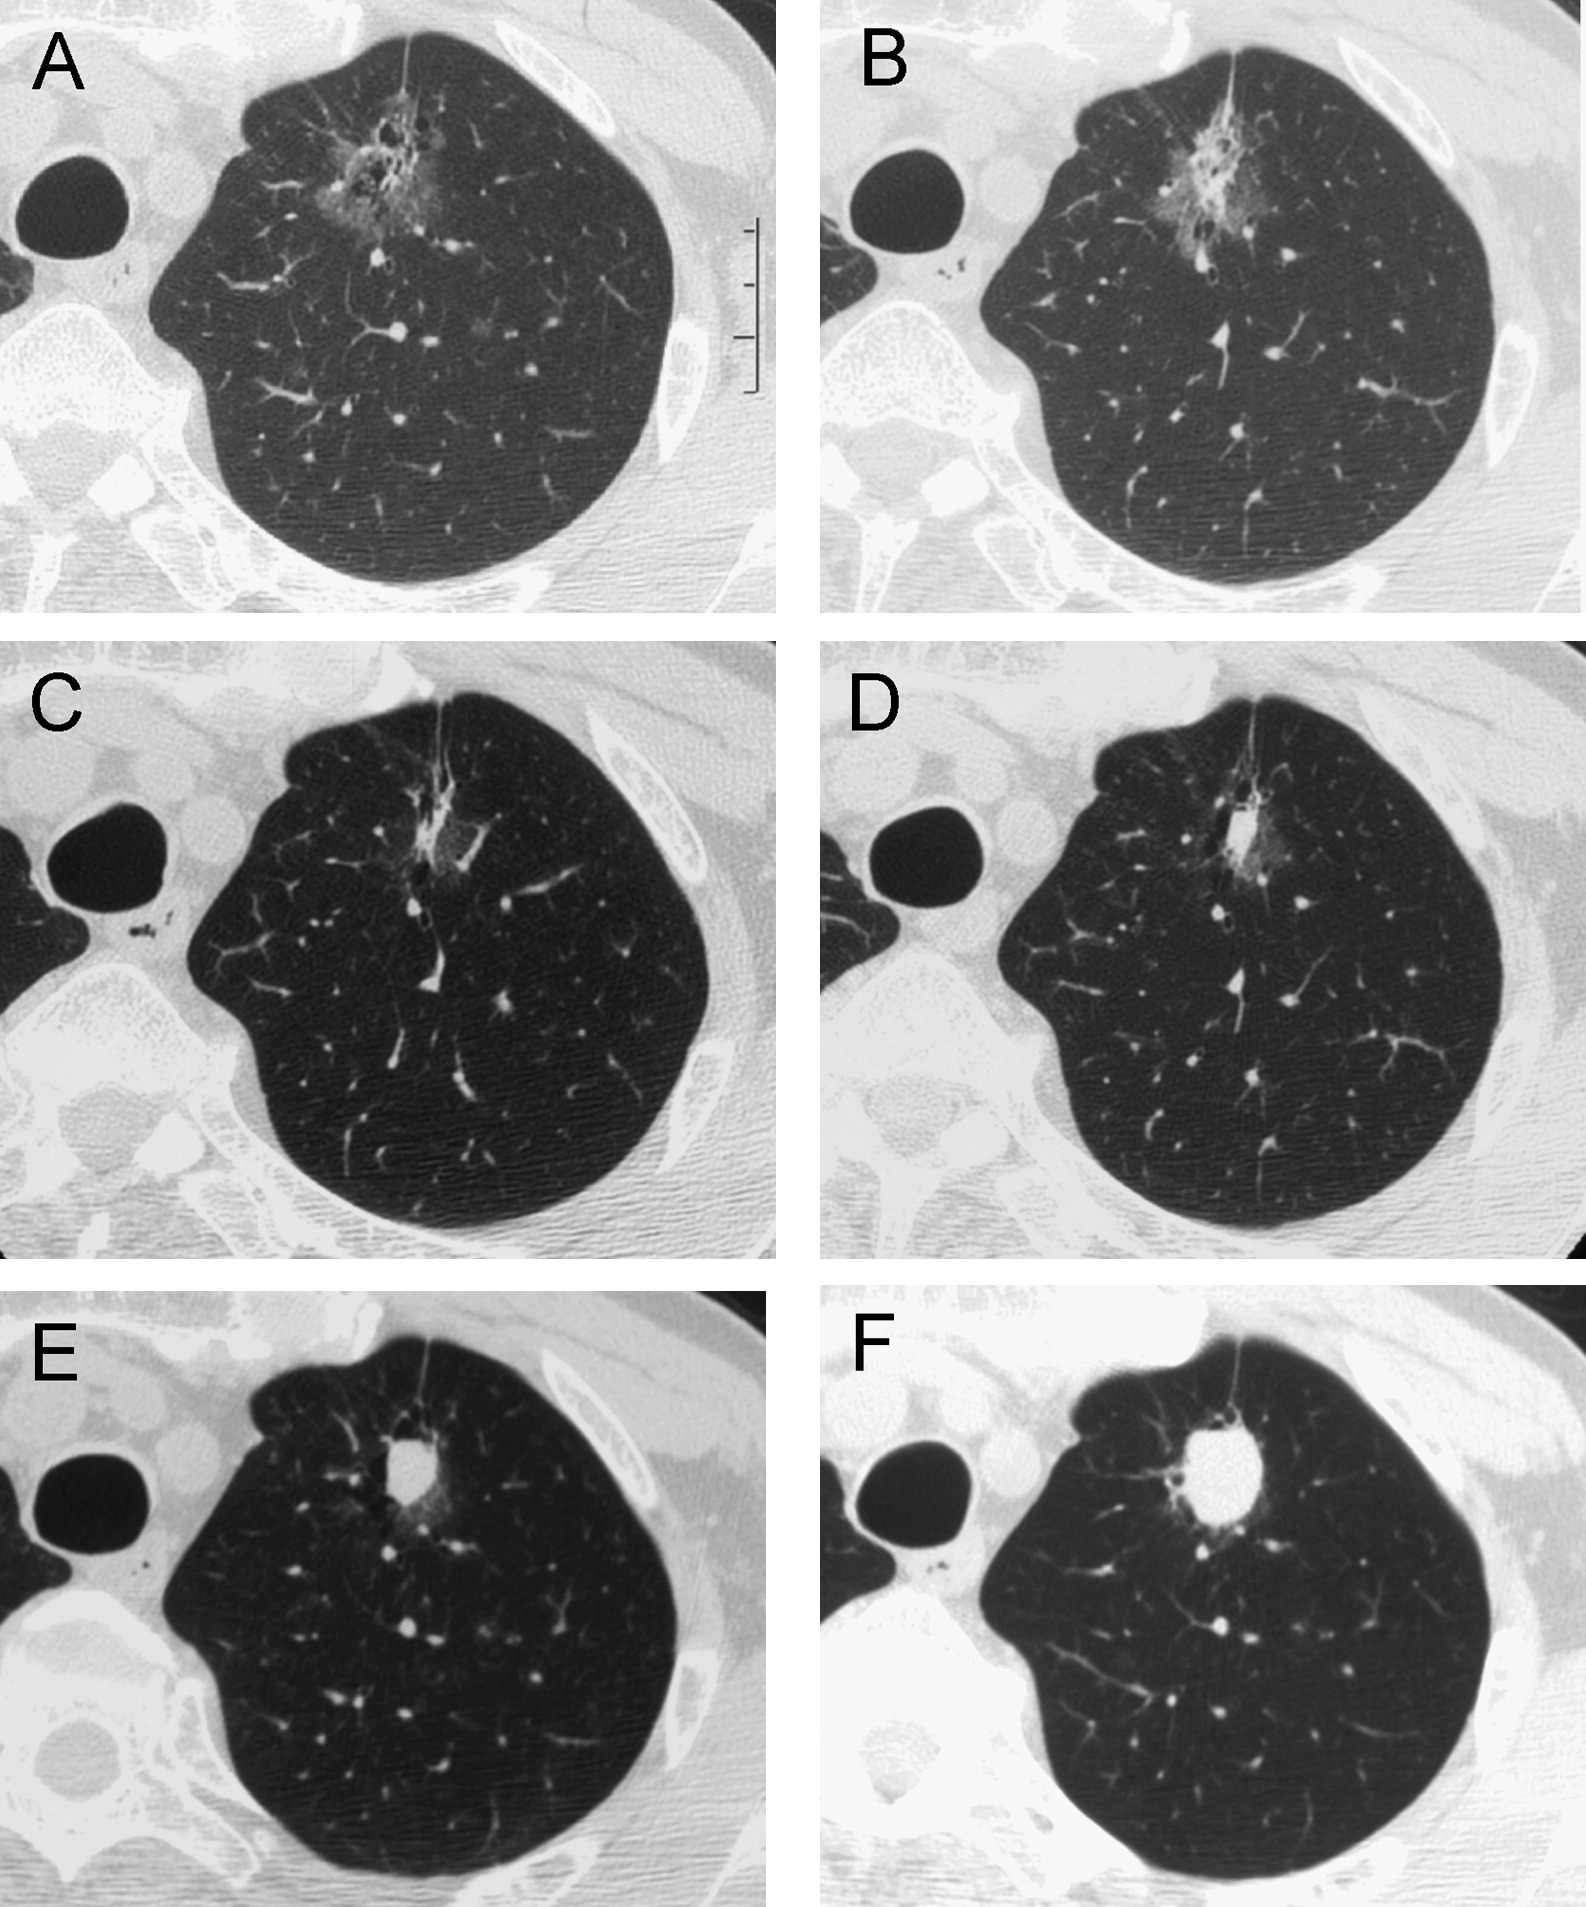

对于GGO(磨玻璃结节)早期肺癌,其生长特性相对缓慢,通常需要较长时间才能增大一倍。因此,对GGO的随访时间一般至少为3年。实际上,仅有约20%的纯GGO在随访过程中会增大或演变为混合型GGO;而大约40%的混合型GGO在随访中会增大,或者实性成分增多,但这个过程通常是相对缓慢的。

肺部磨玻璃影是从微小逐渐生长至较大的,不会一开始就变成巨大肿瘤。在初期(直径小于1厘米),它们通常呈现为纯度较高、密度较低、边缘清晰,此时尚未明确为恶性,可称为纯GGO。经过切除后,多数情况下被证实为腺瘤样不典型增生(AAH,癌前病变),或者是原位腺癌(AIS,无周围血管间质侵犯,不会转移,5年生存率100%),甚至极少数情况下可能是微浸润腺癌(MIA,周围血管间质侵犯距离小于5毫米,也不会转移,切除后,5年生存率100%)。

随着结节逐渐增大和恶化,可能会引起实性成分增加,变得不那么纯粹,称为混合性GGO。有时,还会出现分叶、毛刺、空泡,胸膜凹陷,血管密集等改变,这时多数已经是恶性了,称为浸润性腺癌。这种情况下,肿瘤可能进入人体血管,发生肺内或全身转移。

实际上,在过去我们随访的许多患者中,特别是病灶直径小于5mm的患者,大多数并不会生长。即使少数生长的患者中,纯磨玻璃结节的生长速度通常也非常缓慢,个别病人的生长速度约为每年1mm左右。因此,在纯磨玻璃结节的随访过程中,是非常安全的。

对于混合型磨玻璃结节,如果直径小于8mm,随访也是相对安全的,每3个月进行一次随访,不会影响手术效果。在临床上,一般而言,不会出现目前是小磨玻璃结节,过3个月就变成晚期肺癌而无法手术的情况。